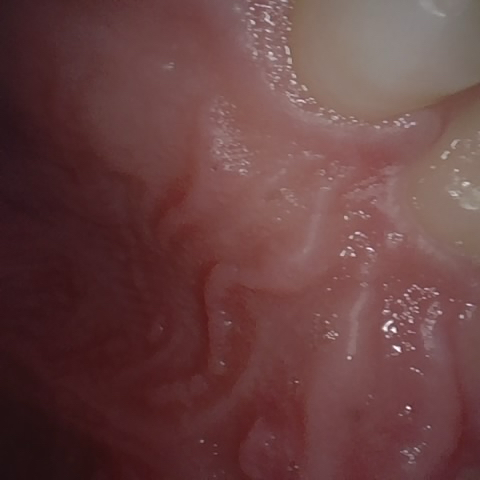

Annotated as "Bad"